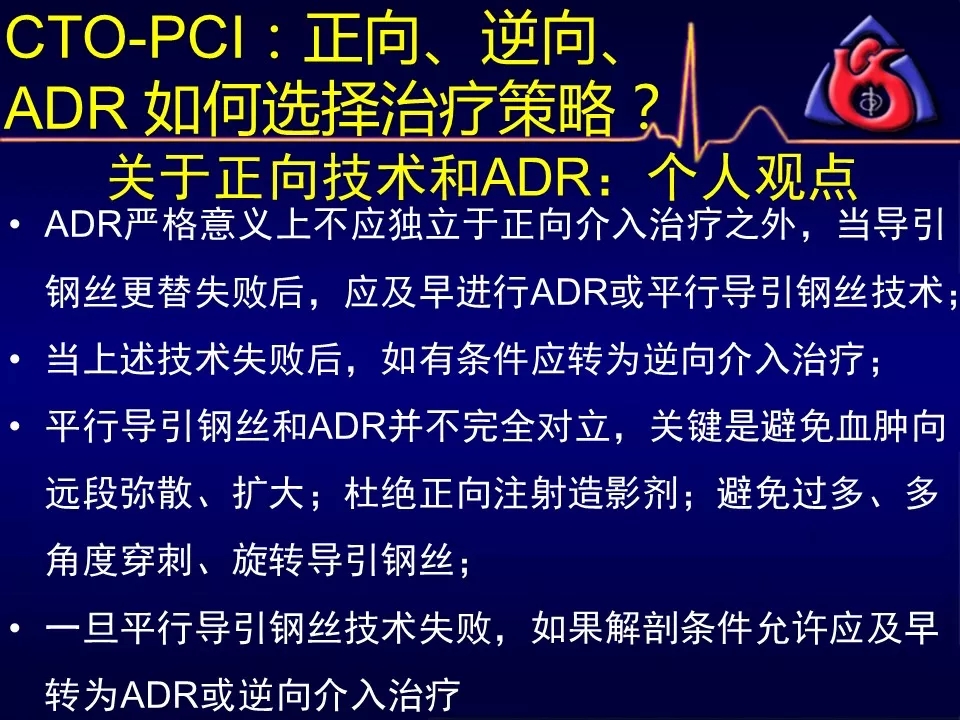

如何选择正向、逆向、IVUS指引及ADR技术?